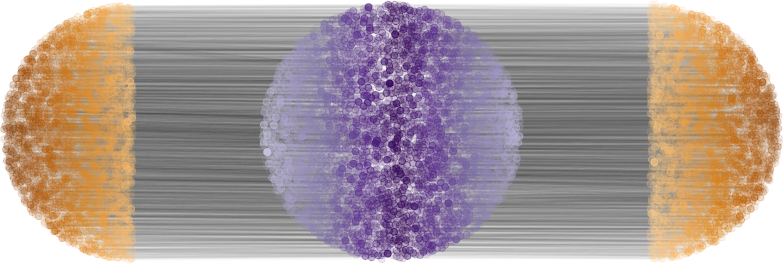

To solve for the optimal transport map between two 3D brain images we extract for each image a point cloud from the intensity volumes. Each point represents a voxel as a point in 3-dimensional space, the location of the voxel. The mass of the point is equal to the intensity value of the voxel, normalized to sum to one over all points. For illustration, Figure 9 shows a single slice extracted from the original volumes and optimal transport maps between the two slices. This 2D problem resulted in point set of approximately points.

|

|

| (a) | (b) |

|

|

| (c) | (d) |